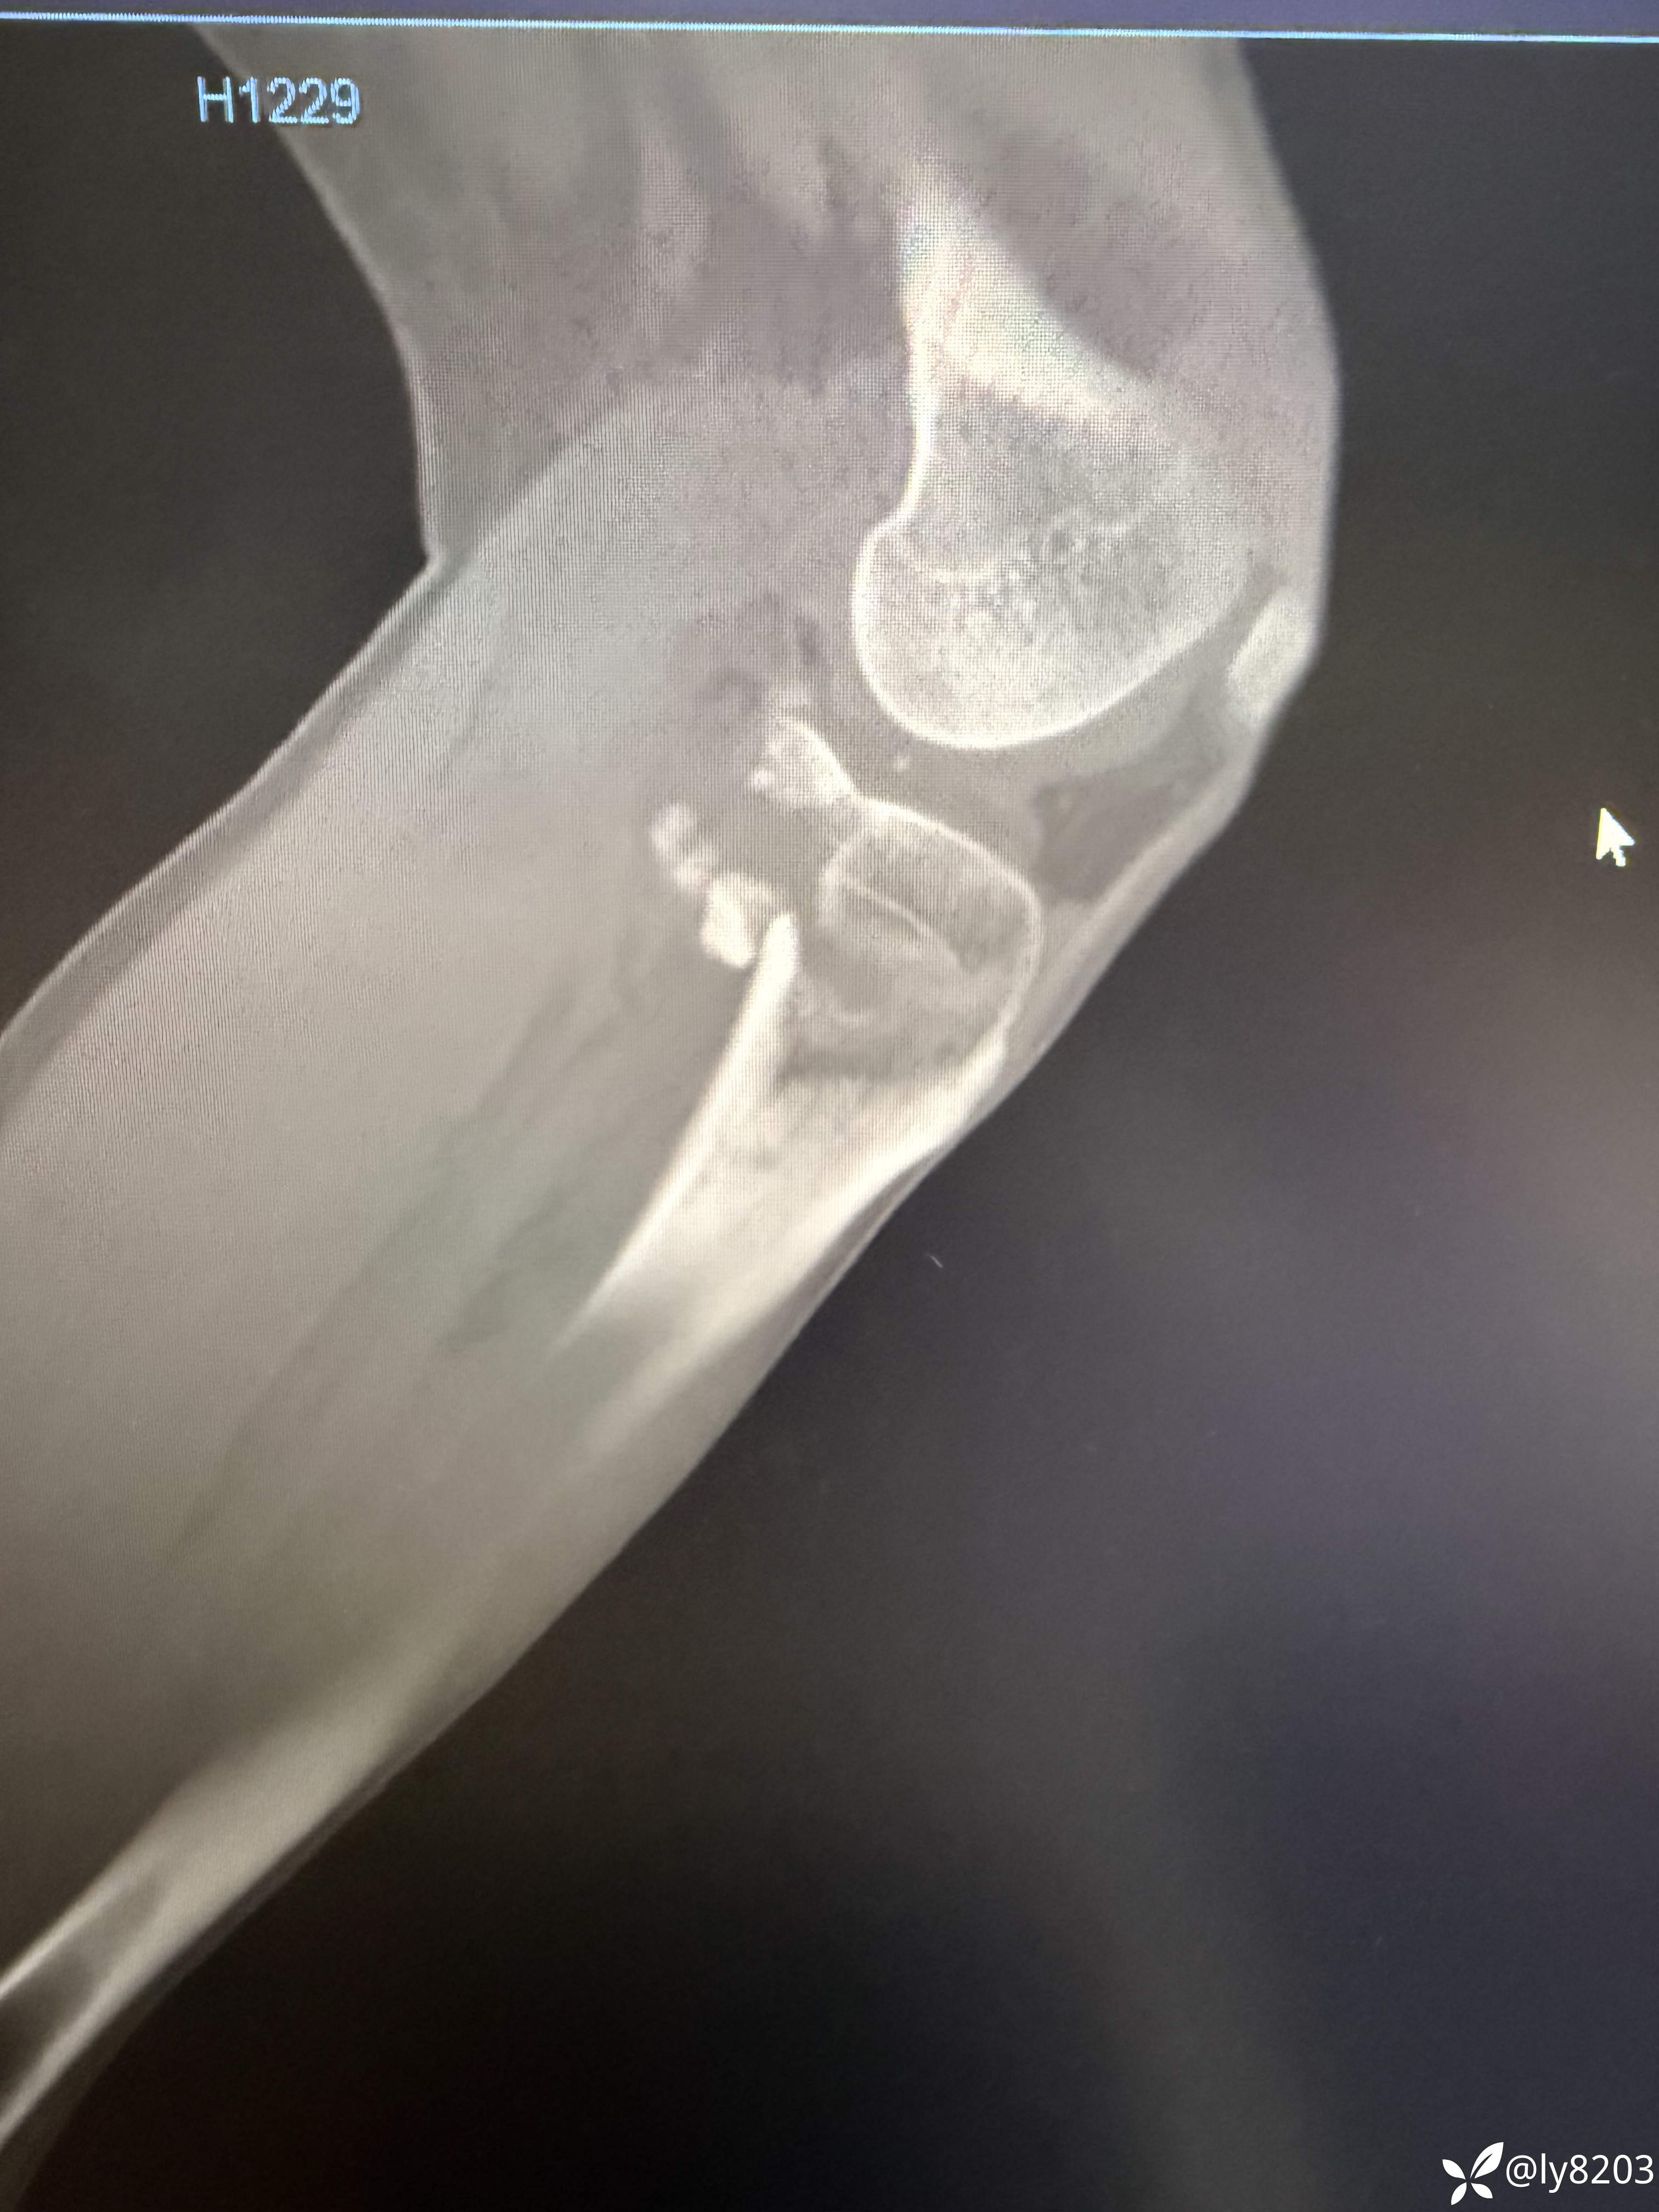

术后影像

术后平片